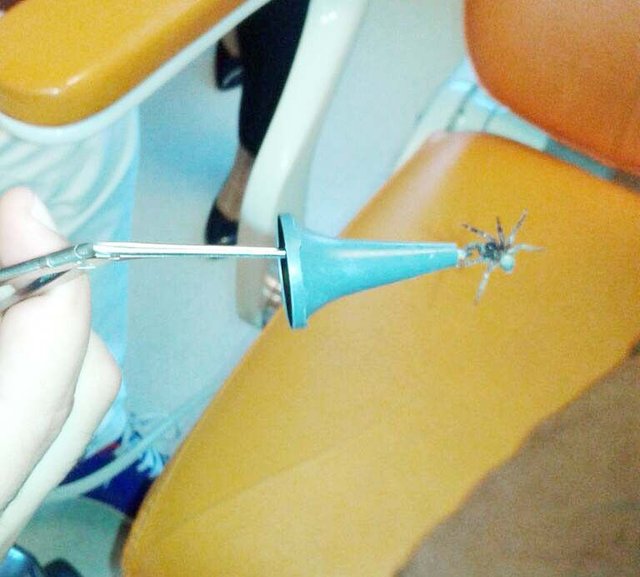

Kulağında hissettiği ağrı sebebiyle Kulak Burun Boğaz Polikliniği'ne ailesi ile başvuran 8 yaşındaki Kenan Ege Bal'ın kulağından canlı bir örümcek çıktı.

Manisa'nın Akhisar ilçesinde kulak ağrısı sonucu hastaneye giden çocuğun kulağından canlı bir örümcek çıktı. Doktora kulak ağrısı şikayetiyle gittiğini kaydeden 8 yaşındaki Kenan Ege Bal, "Köyde tarlaya gitmiştik ve o gece tarlada yattık. Gece uyurken birden kulağımda şiddetli bir ağrı ve kaşıntı oldu. Ağrıdan uyuyamadım ve sabah erkenden annem ve babamla doktora geldik. Kulak burun boğaz doktorunun odasına girdik. Doktorum sağ kulağımdan hareket eden bir örümcek çıkarınca annem, babam ve ben gözlerimize inanamadık ve çok korktuk" dedi.

Sonuçtan dolayı çok şaşkın olduğunu ifade eden baba Mustafa Bal, "Çocuğumuzun kulağından böyle bir şey çıkacağını beklemiyorduk. Yıllardır çiftçilik yapıyorum doktor beyin müdahalesi sonrasında oğlumun kulağında çıkan hareketli örümceği görünce ben bile irkildim. Fakat doktor beyin ilgili ve soğukkanlı yaklaşımı bizi rahatlattı. Ona bu yaklaşımından dolayı çok teşekkür ediyoruz" dedi.

ÖRÜMCEK CANLI OLARAK ÇIKARILDI

Özel bir uğraş sonucu örümceği canlı olarak kulaktan çıkardıklarını ifade eden Kulak Burun Boğaz Uzmanı Op. Dr. Gökhan Karadağ ise "Çevremizde tarımla uğraşan ailelerde daha sık karşılaştığımız bu durumla özellikle yaz aylarında karşı karşıya kalmaktayız.

Kenan Ege'nin kulağındaki örümceğin kulak kanalının derinlerine kaçmasını ve zarar vermesini engellemek amacıyla derhal kulağı özel bir solüsyonla yıkayarak örümceği canlı bir şekilde çıkarttık ve dış kulak kanalını muayene ettik. Muayene sonrasında çok ciddi bir sıkıntı olmadığını tespit ettik ve Kenan Ege'yi ayaktan tedavi ederek önerilerle uğurladık" diye konuştu.